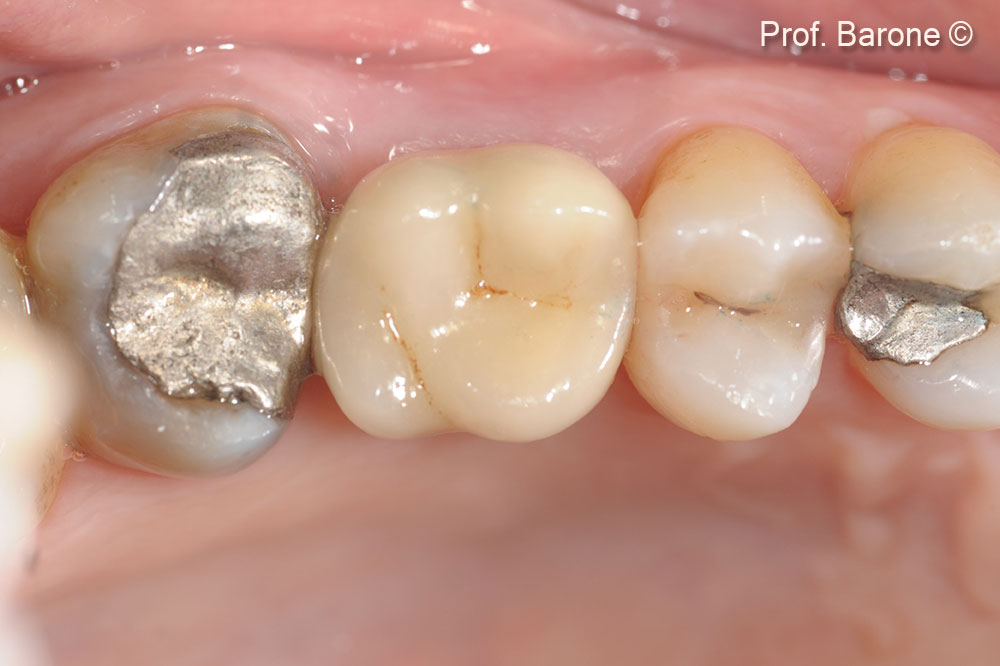

Phục hình cuối cùng, Hình chiếu mặt nhai